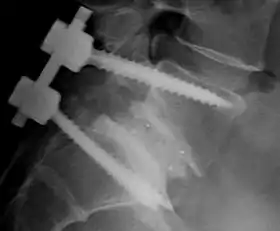

![]() Fusion of L5 and S1 | |

| Other names | Spondylosyndesis |

- Posterolateral fusion is a bone graft between the transverse processes in the back of the spine. These vertebrae are then fixed in place with screws or wire through the pedicles of each vertebra, attaching to a metal rod on each side of the vertebrae.

- Interbody Fusion is a graft where the entire intervertebral disc between vertebrae is removed and a bone graft is placed in the space between the vertebra. A plastic or titanium device may be placed between the vertebra to maintain spine alignment and disc height. The types of interbody fusion are: